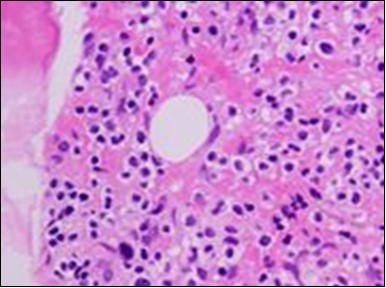

Figure 4.HCL: hairy cells with widely spaced nuclei(20).

The leukaemia cells may enunciate a characteristic immune phenotype, crucial for a confirmatory diagnosis. The peripheral blood mononuclear B cell population may display a kappa or lambda light chain restriction. The phenotype of classic hairy cell leukaemia may be delineated by concurrent, immune reactive CD19+ CD20+,CD 11c+, CD25+, CD103+ and CD123+. An intensely immune reactive CD200+ and a non reactive CD27- antigen may be present2, 4. Evaluation of a trephine bone marrow biopsy and bone marrow aspirate may define the degree of tumour infiltration. A dry tap on account of prominent bone marrow fibrosis may be elucidated at preliminary diagnosis. A decline in the normal haematopoiesis may account for a hypo-cellular marrow in 10% instances. Gradation of cellular infiltrating of the leukaemia within the bone marrow may be appropriately investigated with immune –histochemical stains2, 4. Immune staining for CD20+, annexin 1 and VE1 (a BRAF V600E stain] may validate the diagnosis and precisely analyse the extent of malignant bone marrow infiltration[8]. Determination of BRAF V600E mutation may be critical in therapeutically non responsive individuals with applicable standard therapy or in instances of multitudinous reoccurrences[9]. Deploying inhibitors of BRAF V600E gene may be efficacious in patients impervious to approved therapy. The mutation necessitates a comprehensive scrutiny of the implicated individuals with a sensitive molecular assay which may discern up to < 10% of the hairy leukaemia cells appearing in the peripheral blood smears or bone marrow aspirates diluted with peripheral blood or aspirates elucidating a dry tap[2,4]. Allele specific polymerase chain reaction (PCR) or a next generation sequencing may be optimally employed to circumvent false negative outcomes. If the leukaemia cells are sparse or if particularly sensitive & efficacious molecular techniques are not accessible, the application of appropriate immune histochemical stains to the bone marrow biopsy such as a BRAF V600E mutation stain (VE1) may detect the hairy cells and conclusively diagnose the condition[2,4,10]. Figure 1, Figure 2, Figure 3, Figure 4, Figure 5, Figure 6, Figure 7, Figure 8, Figure 9, Figure 10, Figure 11, Figure 12, Figure 13, Figure 14.